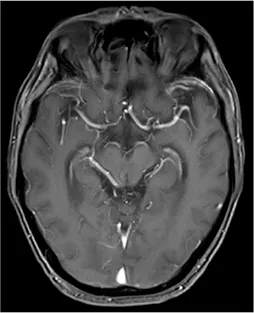

27 neoplastic patients with LC (n = 18), BC (n = 7), GAC (n = 1), and OC (n = 1) presenting with symptoms suggestive of LM, were consecutively enrolled to assess the clinical significance of CTCs and CHCs in LM diagnosis (Figure 2A). The gold standard for LM diagnosis is CSF cytology; nonetheless, due to its low sensitivity, the diagnostic criteria for LM in this study were MRI positivity along with LM-related clinical symptoms, including headache, nausea, vomiting, neurocognitive changes, gait difficulties, cranial nerve palsies, weakness, constipation, urinary retention, loss of consciousness, and seizures. Among the 27 enrolled patients, 24 had MRI findings consistent with meningeal metastasis (Figure 2A). Of the remaining three patients, two had no abnormal meningeal thickening on the MRI, and the other was unable to undergo an effective MRI scan due to the patient’s condition. 24 of the 27 patients underwent CSF cytology, which was performed using Wright-Giemsa staining; however, only 11 patients had tumor cells identified in the CSF (Figure 2A). The clinical characteristics of the 25 patients with confirmed LM are summarized in Table 1.

FIGURE 2

Study design and identification of circulating tumor cells (CTCs) and circulating hybrid cells (CHCs) in cerebrospinal fluid (CSF) by immunofluorescence. (A), Schematic diagram of the study design. MRI and CSF cytology are employed to diagnosis leptomeningeal metastasis (LM) if feasible. CFD-Chip was used to isolate CTCs and CTC clusters from CSF. (B), White blood cells (WBCs) were detected by DAPI+/CD45+/CK- immunofluorescence staining. CTCs were detected by DAPI+/CD45-/CK + immunofluorescence staining. Scale bar, 10 µm. (C), CHCs were detected by DAPI+/CD45+/CK + immunofluorescence staining. Scale bar, 10 µm.